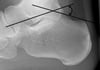

угол Белера

Угол Белера образован пересечением линии, проведенной от верхней части задней пяточной кости к верхней поверхности подтаранного сустава, и линии, проведенной от верхней поверхности подтаранного сустава к верхней части переднего отростка пяточной кости. В норме этот угол равен 20-40°. Угол

Угол Белера определяют на боковой рентгенограмме. Угол Белера образован пересечением линии, проведенной от верхней части задней пяточной кости к верхней поверхности подтаранного сустава, и линии, проведенной от верхней поверхности подтаранного сустава к верхней части переднего отростка пяточной кости. В норме этот угол равен 20-40°. Угол < 20° предполагает перелом.